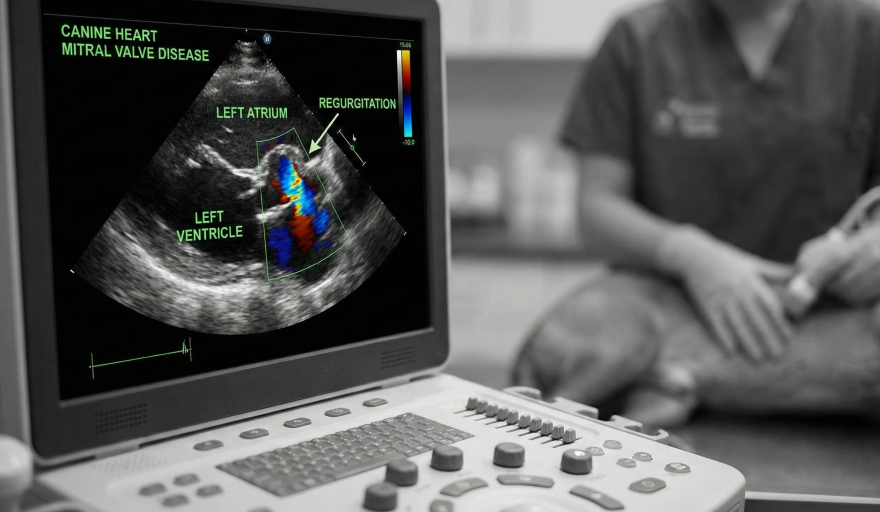

La DMVD es la cardiopatía más frecuente en perros, especialmente en animales pequeños y de edad avanzada. La enfermedad provoca el engrosamiento y deterioro de la válvula mitral, generando reflujo de sangre hacia la aurícula izquierda, agrandamiento cardíaco y, con el tiempo, insuficiencia cardíaca. Aunque no tiene cura, un abordaje terapéutico adecuado permite mejorar la calidad y expectativa de vida de los pacientes.

La técnica TEER surge como una opción prometedora dentro de ese abordaje. Se trata de un procedimiento relativamente reciente, disponible desde 2020 en Asia y desde 2021 en Estados Unidos. La evidencia acumulada indica que alrededor del 95% de los perros tratados se recuperan satisfactoriamente y muestran una reducción significativa de la regurgitación valvular. En casos que ya presentaban insuficiencia cardíaca congestiva, el 80% de los pacientes seguían vivos dos años después del procedimiento, muchos de ellos con menor necesidad de medicación cardíaca.